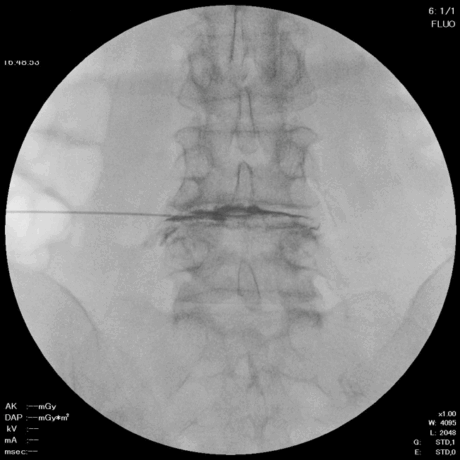

1. 麻酔と穿刺

椎間板造影と同じように椎間板に穿刺し、局所麻酔を行います。

頚椎では前方から、腰椎では後方から、神経を圧迫している部位にアプローチします。

2. ニードル留置

直径約2mmのニードルを椎間板に留置します。